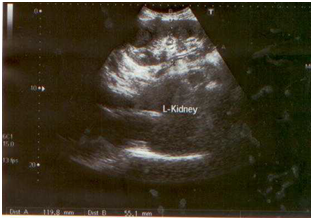

A 30-years old female was admitted to the National Medical Center with the history of persisting fever, headache, weakness, abdominal pain and loss of appetite since last 3 months. A week before arrival to the hospital, she was taking anti tuberculosis treatment (ATT), as prescribed by a local doctor without any actual diagnosis. The consultant after examining patient sent request for blood and urine culture, CBC, liver function tests, urea, creatinine, electrolytes, chest x-ray, ultrasound whole abdomen to the clinical laboratory and radiology department of the hospital respectively. Intravenous fluid infusion and panadol (to manage pain) were given initially to the patient until the investigation results revealed. The blood picture showed 7.9 g/dl (Hb), 424,000 mm3 (PLT) and 7,100 mm3 (WBC) respectively. The renal profile showed urea 10mg/dl and creatinine 0.5mg/dl while liver function tests were found to be within normal ranges. Chest x-ray showed no active lesion excluding pulmonary tuberculosis. The whole abdomen ultrasound showed normal liver, spleen, pancreas, gall bladder, urinary bladder, whereas the right kidney which was of normal size, shape and place. Figure 1A Echogenicity of renal cortex was seen as normal. Corticomedullary distinction was seen intact. But the left kidney was found enlarged (11.9 x 5.5) with perinephric abscess. There was well defined hypoechoic lesion of 6.5 x 3.6 cm noted in upper pole of left kidney extending outside the kidney and filled with thick level echoes inside. Doppler showed no significant flow (Figures 1B & 1C).

Figure 1C Perinephric abscess in left kidney.